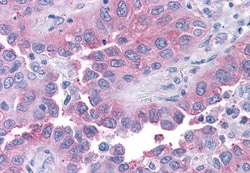

Invitrogen™ TAS1R1 Polyclonal Antibody

| Immunohistochemistry (Paraffin) | |

| Synthetic 16 amino acid peptide from 3rd cytoplasmic domain of human TAS1R1. | |

| Human, Canine, Bovine, Pig, Horse | |